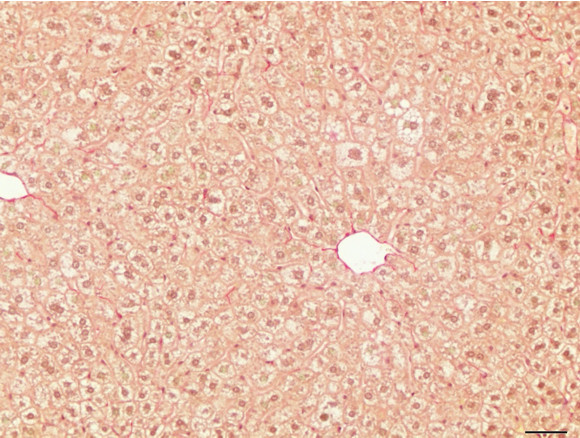

Figure 6: Histopathology for C57BL/6NTac mice placed on D09100310 diet (MASH B6NTac) or kept on chow diet (Control B6NTac) from 6 weeks of age. Animals were on diet for 27, 35 or 53 weeks. Hematoxylin and eosin (H&E) staining illustrates morphological changes including steatosis and infiltration of immune cells. Activated HSCs were identified in liver sections by using a rabbit polyclonal antibody to alpha-smooth muscle actin (a-SMA) (1:500 dilution; ab5694; Abcam, Cambridge, MA) which was detected by an anti-rabbit IgG embedded polymer with embedded horseradish peroxidase and visualized with 3,3′-diaminobenzidine (DAB) chromogen (Agilent, Carpentaria, CA). Hepatocellular lipid droplets were identified by visualization of the lipid-binding protein adipophilin known to be expressed in steatotic livers. Sections of livers were probed using a rabbit polyclonal anti-adipophilin antibody (1:200 dilution; NB110-40877, Novus Biologics, Littleton, CO) which was detected by an anti-rabbit IgG embedded polymer with embedded horseradish peroxidase and visualized with 3,3′-diaminobenzidine (DAB) chromogen (Aligent, Carpentaria, CA). Picrosirius red (PSR) staining illustrates collagen I and III fibers and is used to measure fibrosis. The same individual MASH or control animal is shown for all four stains in a particular time point. Different individual animals were used for each time point (i.e. data is not longitudinal by animal). Histopathology services provided by IDEXX BioAnalytics.